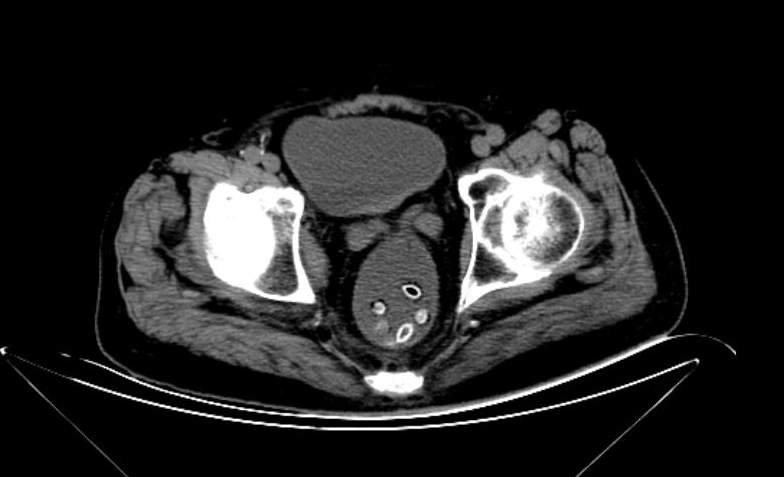

87岁的洪大爷,因脑梗死、高血压于7月2日入住玉环市人民医院。不料,第二天就出现了胃口差、腹部胀痛、排便困难等问题。予以CT检查发现,洪大爷下腹部一串“珠子”。

原来,洪大爷是一位杨梅爱好者,吃杨梅喜欢连籽带果肉一起吞。入院前两天吃了十多颗杨梅,都没有吐籽。

“以前生活苦,父辈们吃水果都不吐籽的,至今还有不少人保留着这个习惯。”神经内科主治医师刘青霞介绍,那堆“珠子”洪大爷未吐的杨梅籽,在肠道里堆积导致肠梗阻。

外科主治医生郑胜利会诊,从他肛门抠出8颗杨梅籽,才解除了肠梗阻的危机。经灌肠处理后,老人才得以舒坦。